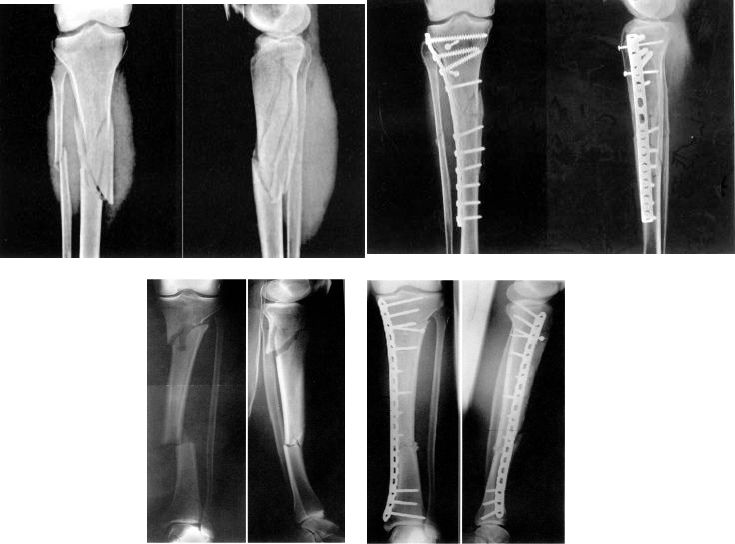

Результат лечения перелома пилона зависит от качества реконструкции сустава и состояния мягких тканей.

Лучшее время для операции зависит от состояния мягких тканей:

Ранняя стадия: операция выполнялась в течение 6-8 часов, длилась 2-3 часа.

Задержка: 7 ~ 10 дней, исчезли отеки и появились морщины на коже.

Четыре традиционных принципа, которых необходимо придерживаться при одноэтапной хирургической реконструкции:

Реконструкция малоберцовой кости

Реконструкция большеберцовой суставной поверхности

Костная пластика

Поддержка костной пластины